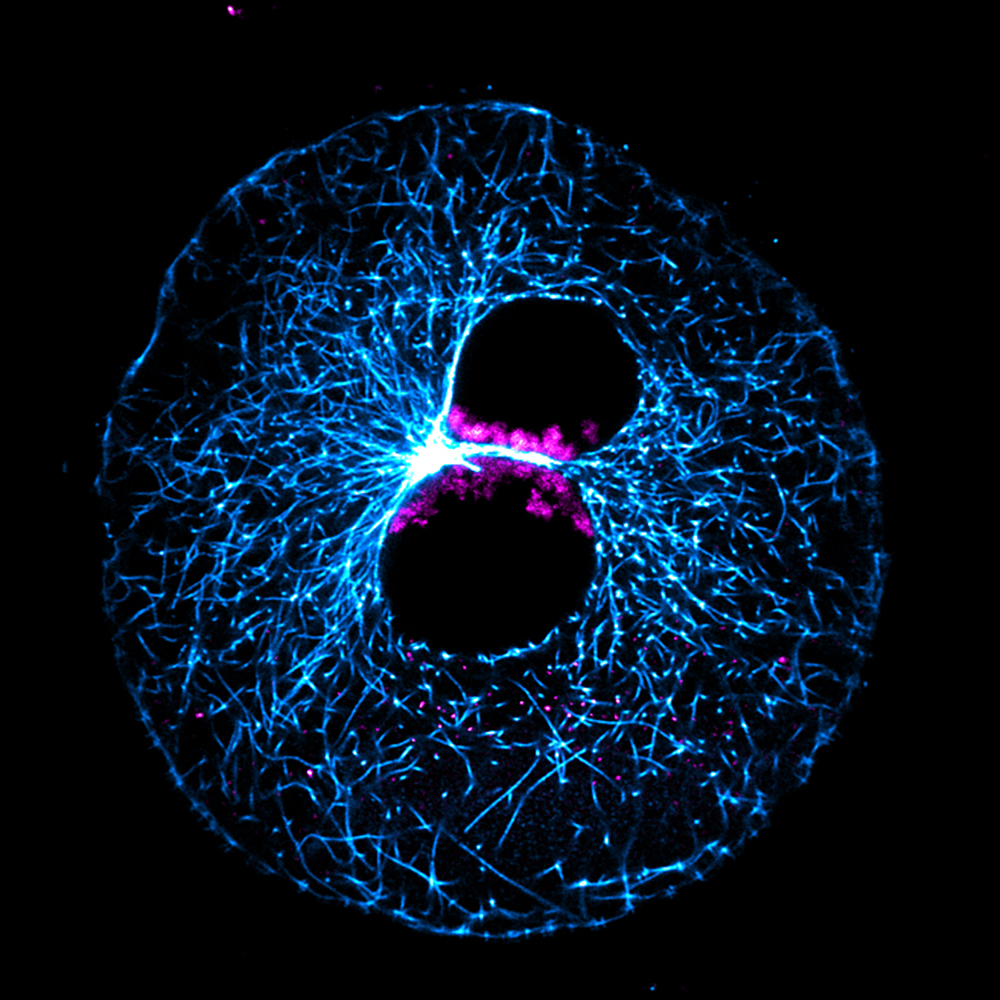

Menschliche Körperzellen besitzen in der Regel 46 Chromosomen, die Träger der Erbinformation. 23 erhält jeder Mensch mit dem Spermium vom Vater, 23 mit der Eizelle von der Mutter. Nach der Befruchtung liegen die elterlichen Chromosomen in der Eizelle zunächst in zwei getrennten Zellkernen vor, die man als Vorkerne bezeichnet. Diese bewegen sich langsam aufeinander zu, bis sie sich berühren. Danach löst sich die Hülle der Vorkerne auf, die elterlichen Chromosomen vereinigen sich. Soweit die Theorie.

Schuhs Team befruchtete die Rinder-Eizellen im Reagenzglas und verfolgte anschließend mittels Lebend-Zell-Mikroskopie, wie sich das elterliche Erbgut vereint. Wie sie herausfanden, versammeln sich die elterlichen Chromosomen an der Grenzfläche der beiden Vorkerne. Bei manchen Zygoten beobachteten die Forschenden allerdings, dass einzelne Chromosomen aus der Reihe tanzten. In der Folge gingen diese bei der Vereinigung des Erbguts quasi verloren, sodass die entstehenden Kerne zu wenige Chromosomen besaßen. Diese Zygoten zeigten bald Entwicklungsdefekte.

Doch wie kommt es, dass sich die Chromosomen oft nicht korrekt versammeln? Auch das konnten die Max-Planck-Forschenden aufdecken, wie Cavazza berichtet: „Bestandteile des Zellskeletts und der Kernhülle orchestrieren, wohin sich die Chromosomen innerhalb der Vorkerne bewegen. Interessanterweise sind das dieselben Elemente, die auch dafür sorgen, dass sich die beiden Vorkerne aufeinander zu bewegen. Wir haben es also mit zwei eng verknüpften Vorgängen zu tun, die lebenswichtig sind, aber häufig fehlerhaft ablaufen. Dass sich ein Embryo gesund entwickelt, hängt damit von einem bemerkenswert ineffizienten Prozess ab.“